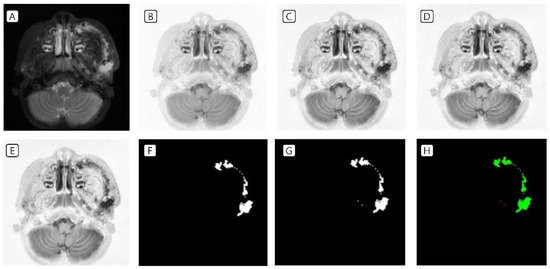

3.1. Cases: Data of the Training Set

3.2. Cases: Data of the Test Set